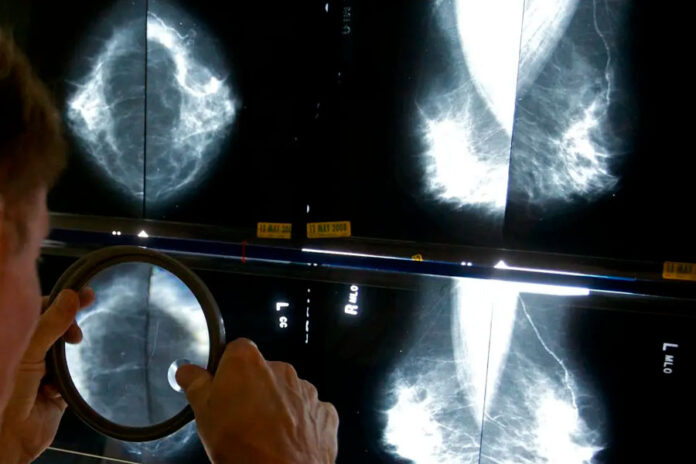

Regular mammograms to screen for breast cancer should start younger, at age 40, according to an influential U.S. task force. Women ages 40 to 74 should get screened every other year, the group said.

Previously, the task force had said women could choose to start breast cancer screening as young as 40, with a stronger recommendation that they get the exams every two years from age 50 through 74.

The announcement Tuesday from the U.S. Preventive Services Task Force makes official a draft recommendation announced last year. The recommendations were published in the Journal of the American Medical Association.

Age 40 is when mammograms should start for women, transgender men and nonbinary people at average risk. They should have the X-ray exam every other year, according to the new guidance. Other groups recommend annual mammograms, starting at 40 or 45.